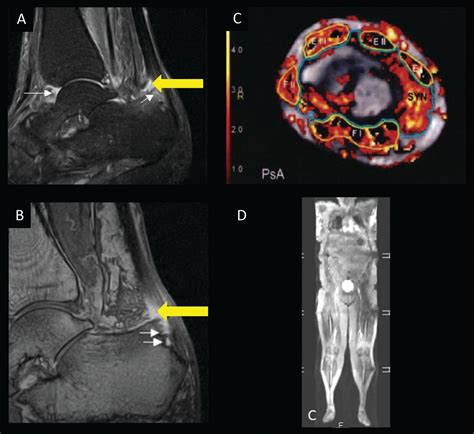

• Imaging studies: X-rays, MRI, or ultrasound to visualize the affected joints and entheses. MRI is particularly useful for detecting inflammation in the sacroiliac joints.